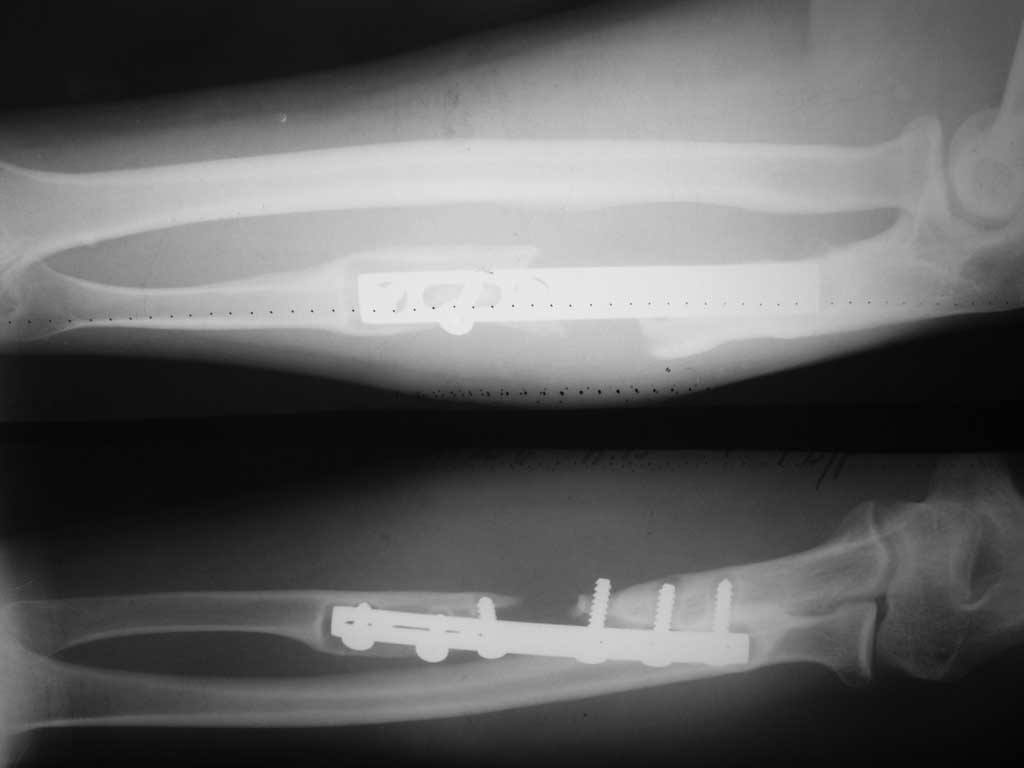

[Ortho] лизис локтевой кости после МОС.

Уважаемые коллеги прошу Вашего совета.Больной 33 лет прооперирован 2 года назад.

Предыдущих снимков нет. Планирую резекция кости в пределах до здоровой кости с замещением

дефекта тутопластом с МОС пластиной с блокируемыми винтами.